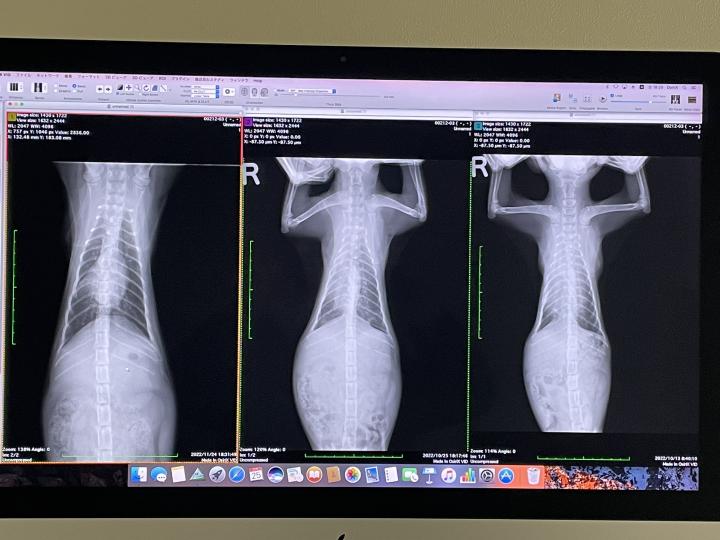

気になってた左肺の機能はほぼ回復

左から

11/24、10/25、10/13

回復してるのがよくわかると思います

最終的に左肺の一部が少し線維化してはいるけれど、心肺機能には特に問題はなし。